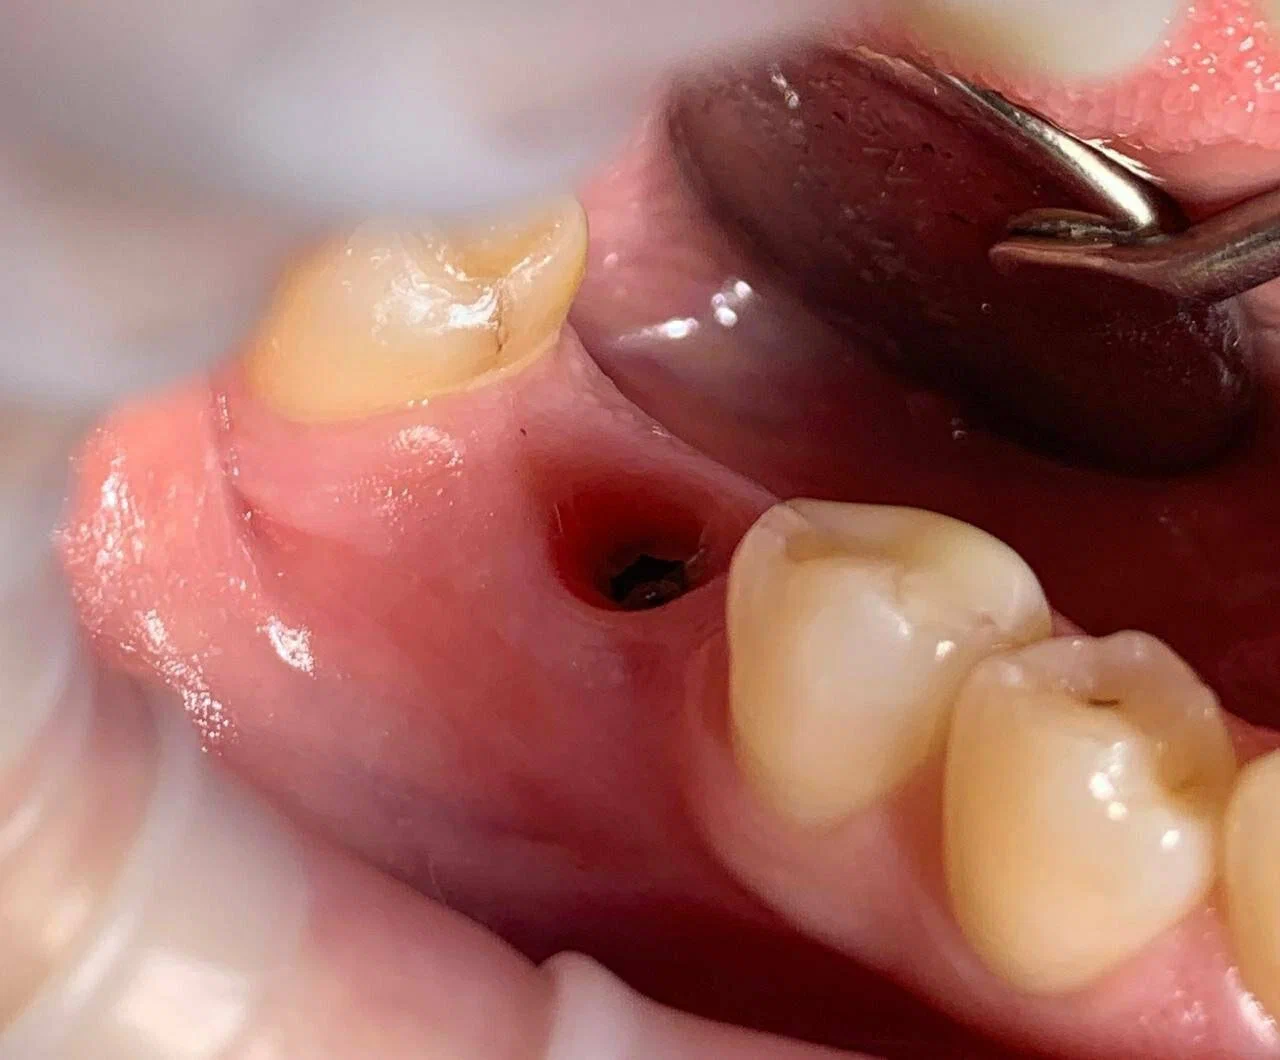

Минимальное хирургическое вмешательство с 3D-шаблоном

Имплантация без разреза десны скальпелем

с технологией микропрокола

Планируем в 3D все этапы операции для установки импланта с точностью до 0,01 мм + восстановление проходит в 3 раза быстрее